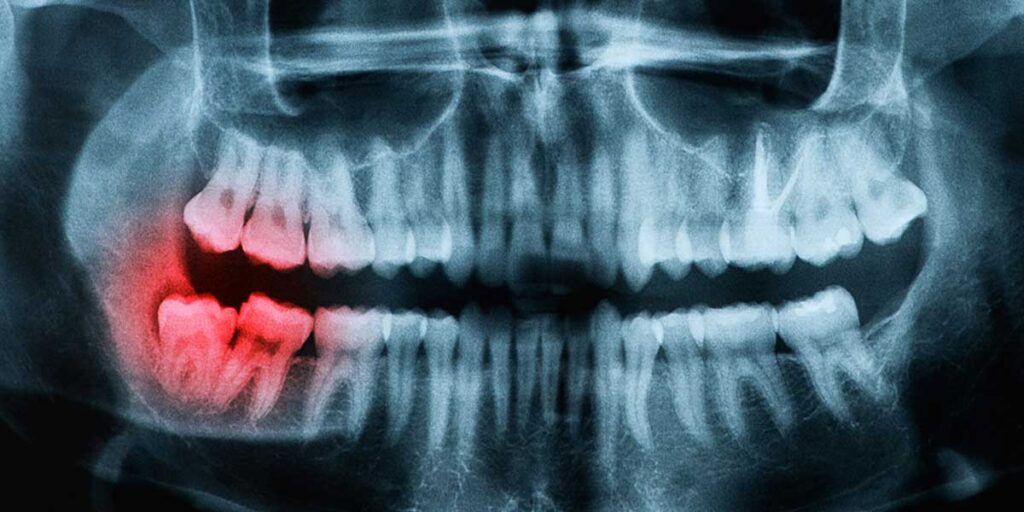

What is Dentoalveolar?

Dentoalveolar surgery focuses on routine issues such as removal, bone shaping, and minor soft tissue repairs. It actually means nearly 50% of all minor surgeries completed in our office setting. Anyone who has ever experienced a toothache will understand the importance of dentoalveolar surgery.